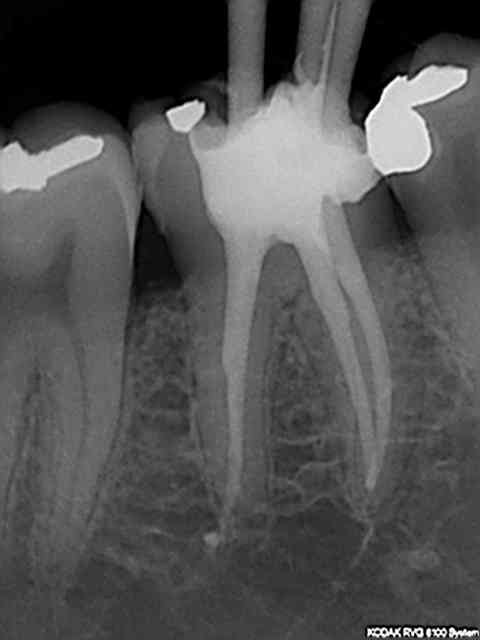

15 mn endo + sc33+ emp

test effectué : pulpec commencée à 11h10 et rx à 11h 30)))